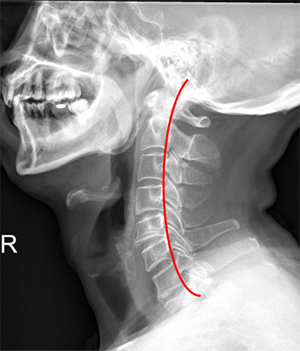

<ÀÏÀÚ¸ñȯÀÚ X-RAY / Á¤»ó ¸ñ X-RAY >

ÃÑ 33°³ÀÇ Ã´Ãß Áß °¡Àå À§¿¡ À§Ä¡ÇÑ °æÃß(¸ñ»À) 1¹øºÎÅÍ 7¹ø. Á¤»ó °æÃß´Â CÀÚ ÇüÅ·ΠµÇ¾î ÀÖÀ¸³ª ÀÏÀÚ º¯Çü µÇ¾î ÀÖ´Â »óŸ¦ ÀÏÀÚ¸ñ ÁõÈıºÀÌ¶ó ¸»ÇÏ¸ç ¸»¸ç ÈçÈ÷ °ÅºÏ¸ñ ÁõÈıºÀ̶ó°íµµ ÇÕ´Ï´Ù. º¸Åë ¿¬·É´ë°¡ ³ô°í ±ÙÀ°·®ÀÌ ºÎÁ·ÇÒ ¼ö·Ï ½±°Ô ¹ßº´ÇÏÁö¸¸ ÃÖ±Ùµé¾î ÄÄÇ»ÅÍ ¹× ¾É¾Æ¼­ ¾÷¹« ¹× »ýȰÀ» ¸¹ÀÌ Çϸ鼭 ¿¬·É, ¼ºº°¿¡ °ü°è¾øÀÌ ¹ß»ýºóµµ°¡ Áõ°¡Çϰí ÀÖ½À´Ï´Ù.